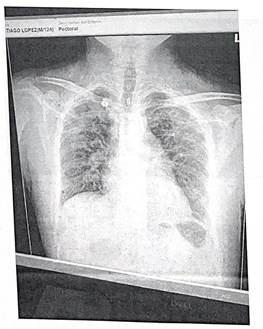

En la tabla 2 se pueden analizar los estudios paraclínicos realizados en agosto de 2023. En los estudios de imagen, la radiografía de tórax posteroanterior de agosto de 2023 (imagen 1) mostró opacidades bilaterales de predominio apical, tipo 2 de la Clasificación Internacional de la OIT. La tomografía computarizada (TC) toracoabdominal del mismo mes (imagen 2) evidenció opacidades bilaterales formando masas, principalmente en pulmón derecho, sin cavitaciones, desplazamiento bronquial por efecto de masa, nódulos subpleurales, alteración de arquitectura pulmonar; y una TC posterior realizada en clínica privada reportó imágenes hiperdensas en lóbulos superiores, probable cavitación ocupada en lóbulo superior derecho, fibrosis y patrón reticular grueso sin derrame pleural. Como parte del protocolo de estudio, se le realizaron las pruebas de función pulmonar donde se reportaron en febrero de 2024 una CVF (capacidad vital forzada) y VEF₁ (volumen de aire exhalado durante el primer segundo de la maniobra espiratoria forzada) al 60%, y en marzo de 2024 CVF 42% y VEF₁ 45%, confirmando deterioro funcional severo (imagen 3).

Imagen 3.

Espirometría

Nota: Espirometría con patrón restrictivo.